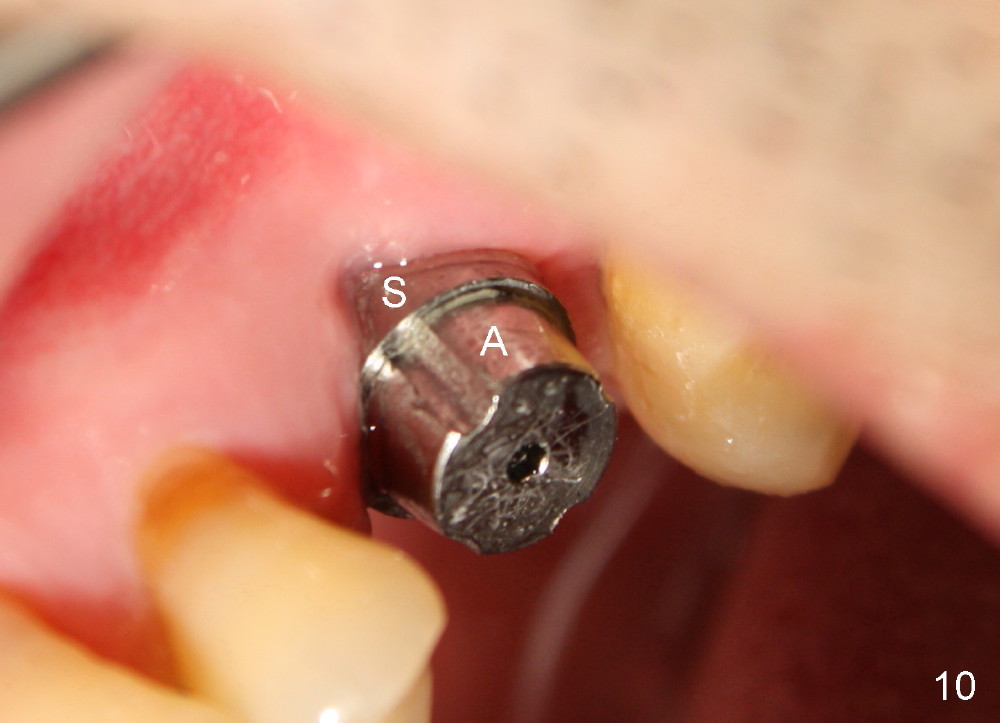

PA taken 3 months postop (Fig.9) shows bone graft in the mesial gap (*). Clinically the implant surface is less exposed buccally (Fig.10) than palatally (Fig.11 *).